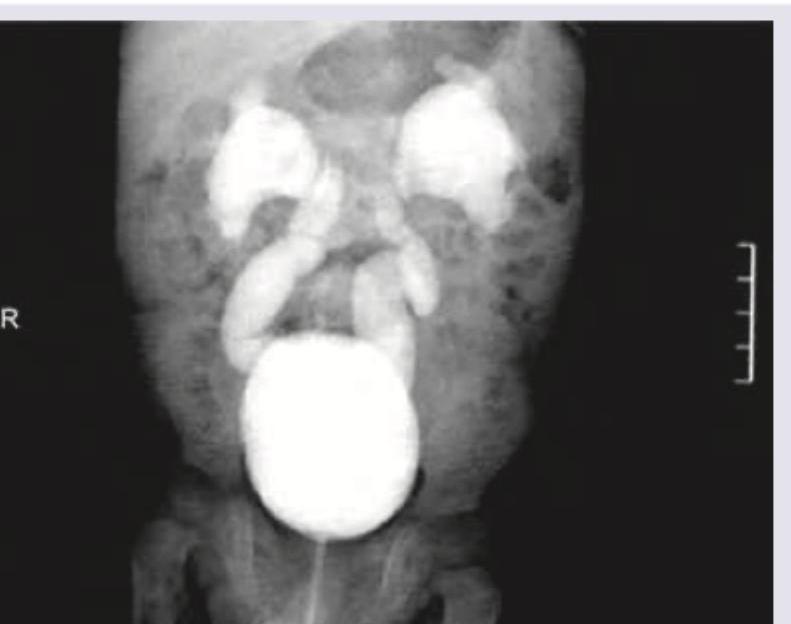

A 50-year-old man went for his annual medical check-up. CT scan is shown below. Diagnosis is?

Explanation: ***Renal angiomyolipoma*** - The CT scan shows a renal mass with areas of **macroscopic fat density**, which is the hallmark of an angiomyolipoma. - Angiomyolipomas are **benign renal tumors** composed of variable amounts of smooth muscle, vascular tissue, and mature adipose tissue. *Renal cell carcinoma* - While renal cell carcinoma can present as a solid renal mass, it typically does **not contain macroscopic fat**. - It usually enhances heterogeneously with contrast and may show areas of necrosis or hemorrhage, but the presence of fat rules out typical RCC. *Renal cyst* - Renal cysts are typically **simple fluid-filled structures** with very low attenuation values (close to water) and **do not contain solid components or fat**. - They also have thin, imperceptible walls and do not enhance with contrast. *Rhabdomyosarcoma* - Rhabdomyosarcomas are **malignant soft tissue tumors** rarely found in the kidney, and would appear as a solid, often heterogeneous mass on CT. - They do **not contain fat** and are aggressive tumors, often associated with a different patient demographic (e.g., children).